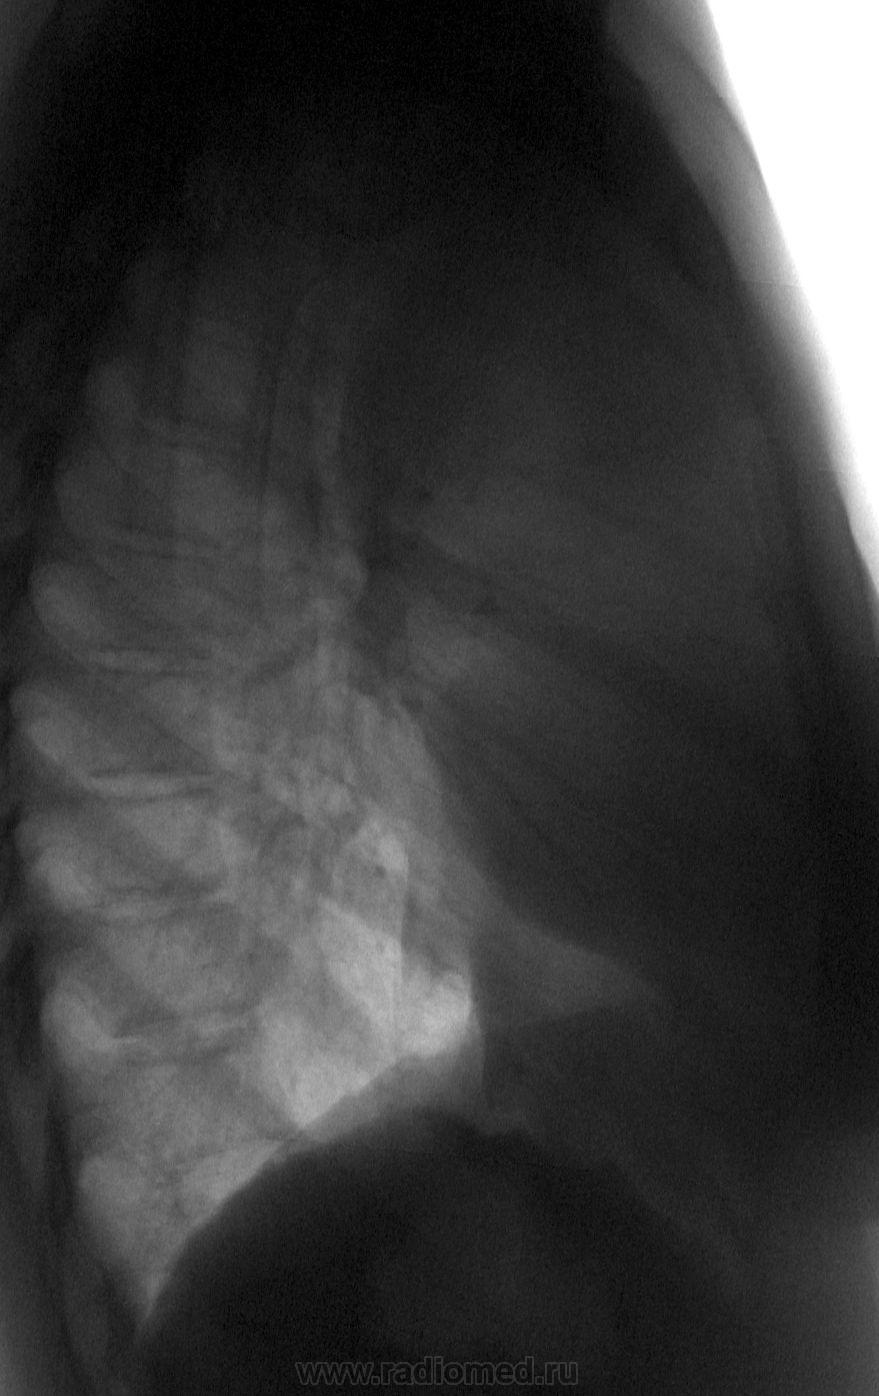

Нахожусь в подавленном настроении от вчерашнего случая. Несколько лет назад я подарил свой немецкий аккордеон, который не брал в руки более 30 лет после окончания муз. школы, практически незнакомой, подающей надежды девчушке, которая в силу обстоятельств (у родителей свои семьи) вынянчена и воспитывается бабушкой, санитаркой по професии. И вот сегодня она, победитель ряда местных конкурсов, выезжает на конкурс в Финляндию (визы, билеты и т.д. все с потугами бабушкой оплачено), а вчера она делала первую в своей жизни флюорографию. Отмечает тяжесть за грудиной. Низкий гемоглобин, высокое СОЭ (со слов бабушки).

Вроде про миастению  ни слова, но эдакий "хвостик" по нижнему контуру, более характерен для тимомы.

Пациентке надо провести КТ, возможно, с контрастным усилением. Имеется образование средостения, более выраженное справа, но его характер неясен. Я бы в первую очередь не предполагала бы тимому... Она едит поедзом или летит самолетом?

Какая-то лимфома. Лежала она и у нас в детской обл., и в столице в ОхМаДете. Волей-неволей, но это было у меня на слуху: то по FM радио услышу призыв на сбор средств на лечение, то по одному из каналов TV очень мной уважаемый певец, шоумен, соирался посетить ее в клинике и подарить аккордеон (не знаю, выполнил ли?), назвав ее очень талантливой девочкой...